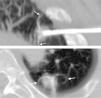

Respuesta radiológicaComo ya se ha comentado, en el control inmediato al tratamiento se evaluó la presencia de un halo de características en vidrio deslustrado que circundase el contorno del tumor. Dicho hallazgo se cotejó con las imágenes obtenidas inmediatamente después de la punción, ya que las opacidades en vidrio deslustrado pueden ser secundarias a hemorragia alveolar por la manipulación de la aguja dentro del parénquima. A las 24h del procedimiento la imagen que se obtiene como respuesta al tratamiento se define como "fenómeno de la escarapela" (fig. 4). En los controles sucesivos, en la lesión tratada se valoraron el tamaño del nódulo, la captación del contraste y la presencia de cavitación.

Signo de la escarapela: en el control realizado a las 24h se aprecia el nódulo tratado, de características hiperdensas (secundario a la necrosis coagulativa), con un halo de baja atenuación (flecha hueca) rodeado por otro halo de mayor densidad (flechas). Mínimo derrame pleural secundario (punta de flecha).